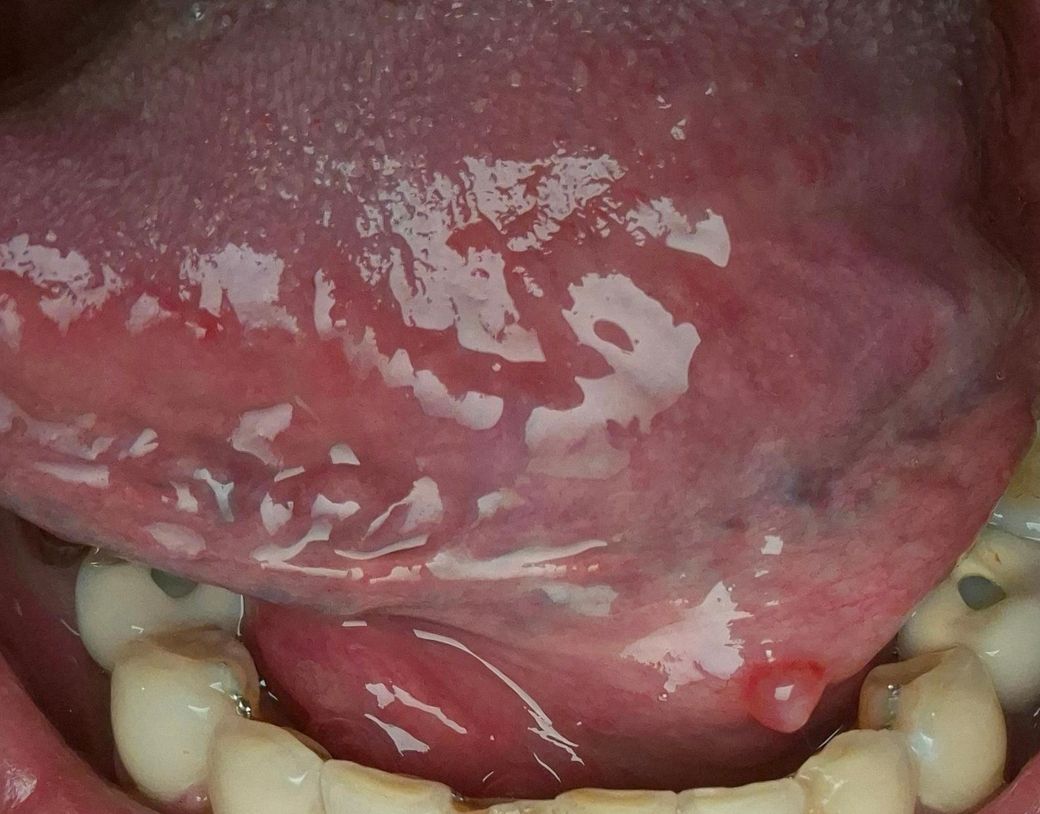

• 1번 째 사진

• 사진상 설하부(혀 밑) 점막에 2–3 mm 정도의 둥근 융기 병변이 보이며, 표면은 비교적 매끈하고 반투명 또는 약간 창백한 색조로 관찰됩니다. 통증이 없고 이물감만 있는 점을 고려하면 다음 가능성이 우선입니다.

가장 흔한 것은 점액낭종입니다. 소타액선(설하선 또는 하악설하선)에서 분비되는 점액이 배출되지 못하고 고여 생기는 병변으로, 설하부에 비교적 흔합니다. 크기가 작고 통증이 없는 경우가 많으며, 시간이 지나면서 커졌다 작아졌다 하거나 자연 소실되기도 합니다.

감별로는 소타액선 관 폐쇄(침샘관 막힘) 또는 초기 타석증 가능성도 있습니다. 다만 타석은 보통 식사 시 통증이나 부종이 동반되는 경우가 많아 현재 양상과는 다소 거리가 있습니다. 그 외 드물게는 섬유종, 유두종 같은 양성 종양도 가능하지만, 사진상 전형성은 점액낭종 쪽이 더 높습니다.